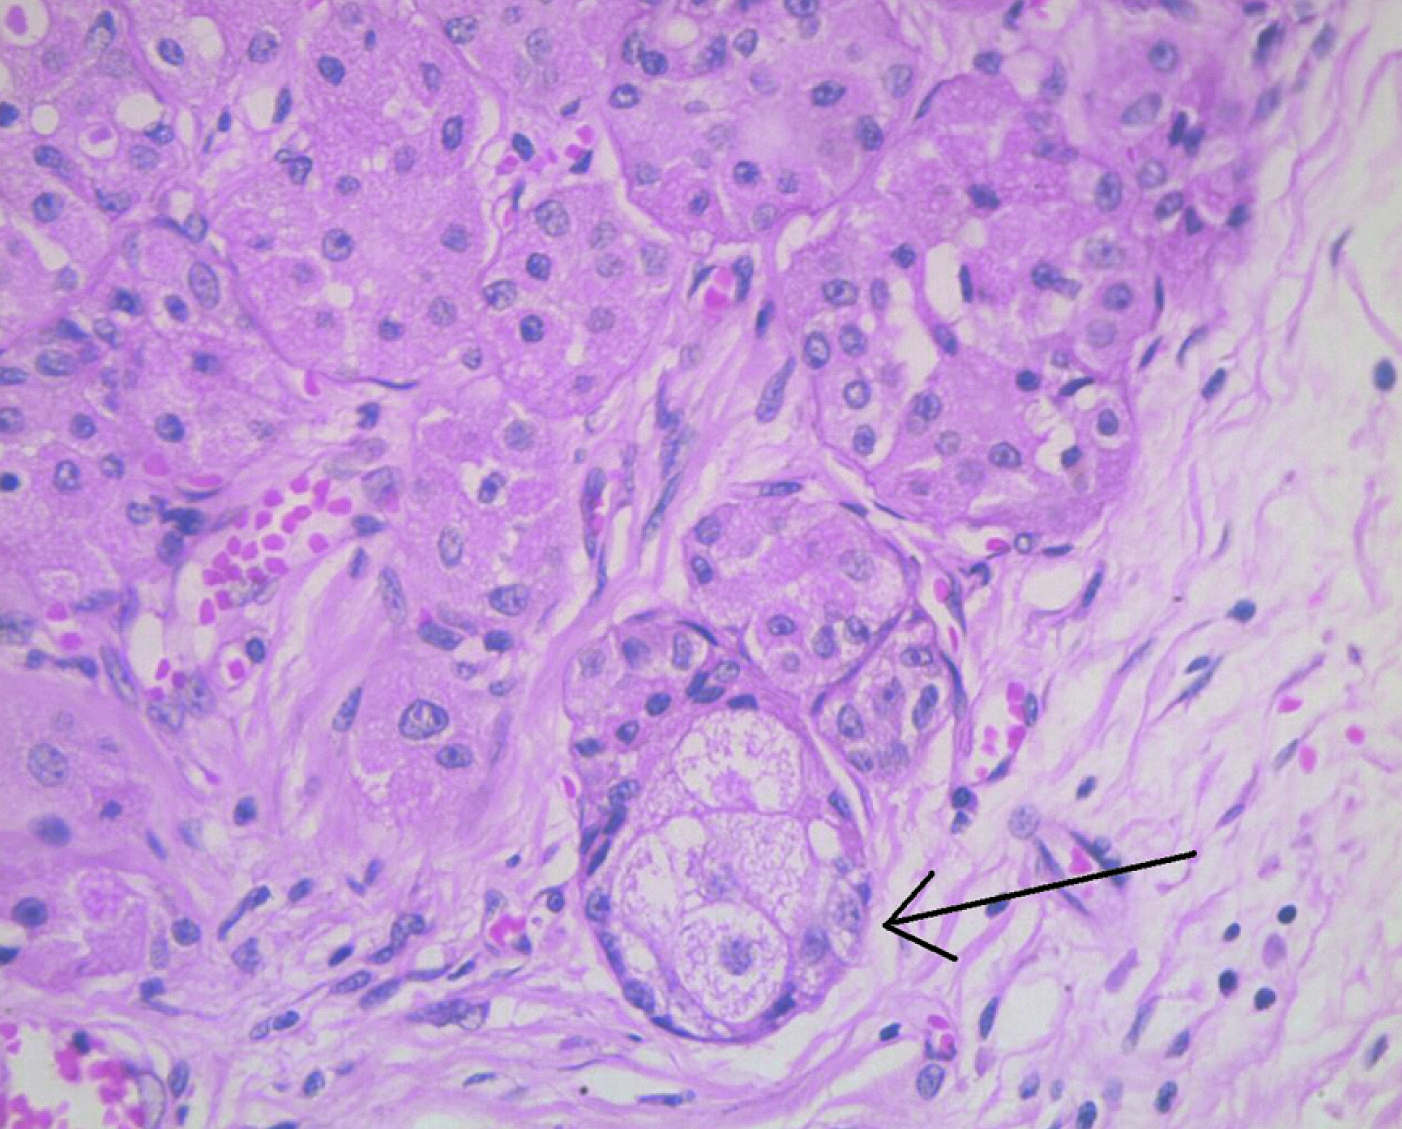

Left salivary gland was enlarged with a large fatty lesion, 55mm x 45mm x 20mm, having a large mural component. Lesion had solid component in it measuring approximately 27 x 17 mm. with a few mottled densities [Table/Fig-1]. There was no significant lymphadenopathy. Surgery was done under general anaesthesia. Patient was positioned on a shoulder roll with head tilted to right side. Painting with betadine lotion was done followed by drapping. The incision was made in the skin crease 5cm below the angle of mandible and deepened through platysma. Both superficial and deep lobes were identified with preservation of mandibular nerve and hypoglossal nerve with ligation of facial artery and facial vein. A 5 × 5 cm large mass arising from the left submandibular gland was excised and submitted for histopathological examination. After securing complete hemostasis, cervical fascia and skin flaps were sutured back in position. Grossly, the tumour was lobulated, encapsulated mass with well-defined brown areas and adjacent greasy-yellow soft areas [Table/Fig-2]. Histopathology examination revealed circumscribed tumour composed of lobules and sheets of oncocytes [Table/Fig-3,4]. Also, present were sheets and lobules of mature adipocytes, some of which are entrapped by the oncocytic nodules [Table/Fig-3,4]. There was patchy periductal chronic inflammation and fibrosis. There was focal sebaceous metaplasia at the edges of oncocytic nodules [Table/Fig-5]. There was no evidence of lymphovascular or perineurial invasion or any extra capsular invasion. Immunohistochemistry was not indicated in this case due to obvious morphological findings, which were consistent with those mentioned in the literature. On a telephonic follow up, no recurrence of symptoms so far. Patient is due for a yearly follow-up during which imaging will be carried in case there is any clinical evidence of recurrence.

H&E stain, 40x magnification showing focus of a sebaceous metaplasia